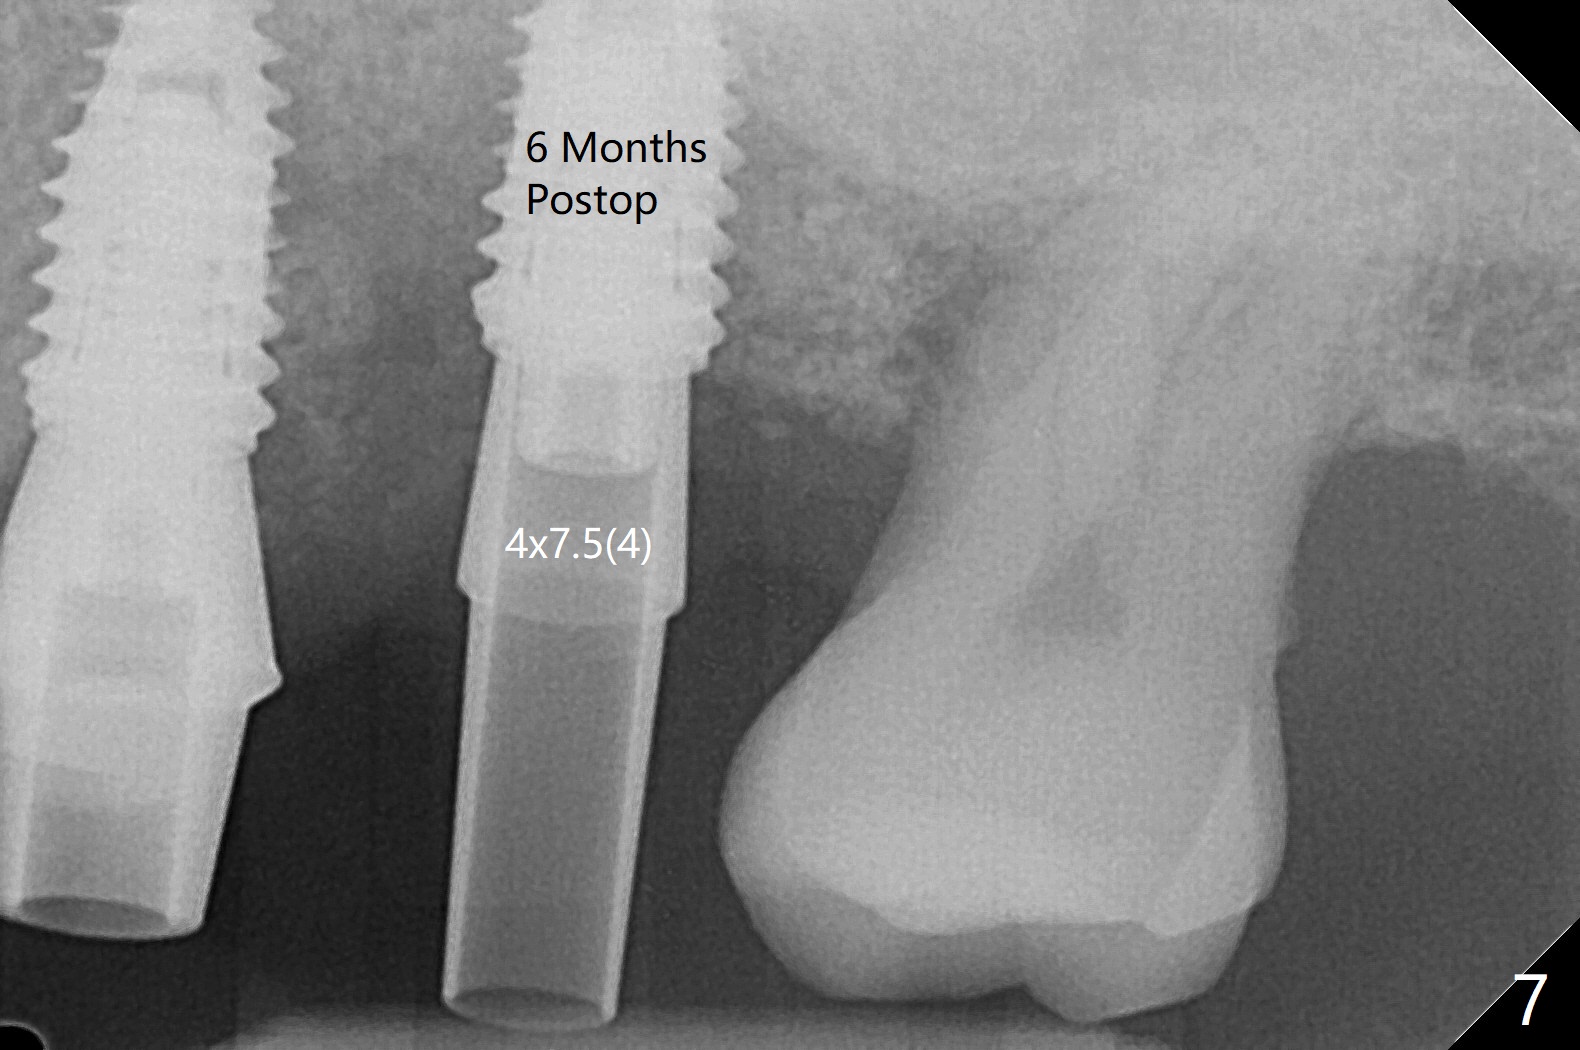

左上六植牙第三次失败后五个月,牙槽嵴宽度尚可,切开后放置导板,3.2乘19毫米园钻头好像接近上颌窦底板(图一),但是粘性骨块和4乘10毫米报废植体就不能进入上颌窦(图二),最后不得不使用3毫米Bicon骨凿,之后同一个报废植体就似乎进入上颌窦(图三),4.5乘8.5毫米正式植体植入深度和稳定性均正常(图四),腭侧植体稍微暴露,放置愈合螺丝后,放置骨粉和PRF膜,缝合,左上5植体放置5.7x4.5(4)毫米基台,固定牙周敷料。术后5.5个月植体好像整合(图五),缺牙间隙特别小,5临时牙冠(P)必须取出才能切开暴露植体,放置5.5x5毫米愈合基台(图六)。伤口愈合后,必须做渐进性负荷,之后做简单局部矫正,推7往远中,6缺失3年,7往近中倾斜移位。两周后牙周敷料脱落,伤口愈合,放置修复基台,故意将基台平面朝远中,足够空间制作临时牙冠(图七)。调整基台长度(比较图七,八)。制作连体牙冠(5,6),有意提高5牙冠高度,使左上7不与对合牙接触,有利于远中移位(图九)。也要在对侧提高咬合(图十)。局部矫正一个月后,磨去右侧咬合垫和磨短左上5,6临时牙冠,前牙还不能完全接触(图十一)。1-2星期前牙开合自行消失,取模做左上5,6牙冠。局部矫正似乎使左上7远中移位大约3毫米(比较图十二,十三)。粘固拧紧后(20 Ncm)14号牙牙冠咬合增高,拍摄根尖片(图十三),两个基台好像仍然完全就位,然后调整咬合。